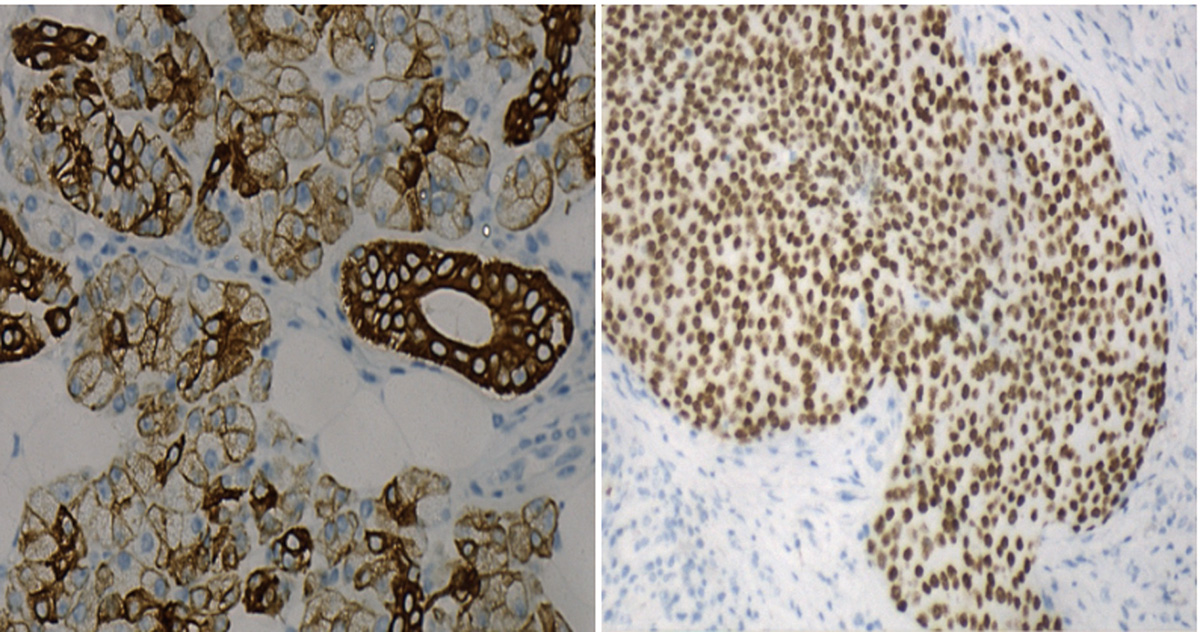

毛母质癌是一种非常罕见的低度恶性肿瘤,具有基质分化的特点,由于临床上极为罕见,极易漏诊、误诊,目前尚缺乏标准的治疗方案。现报道1例头皮毛母质癌并腮腺淋巴结转移患者,在术后进行放疗及顺铂同步增敏治疗后,局部转移病灶取得了完全缓解。